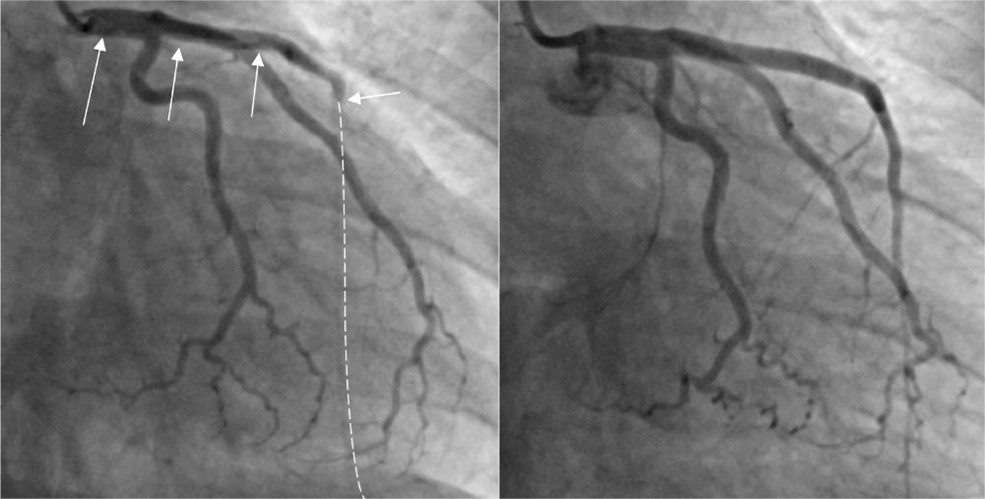

По результатам КАГ (рис. 2): тип кровообращения правый. В стволе левой коронарной артерии (ЛКА) — спонтанная диссекция типа «B» от первой трети, переходящая на переднюю межжелудочковую ветвь (ПМЖВ). Диаметр ствола ЛКА — 5,5 мм. В ПМЖВ — диссекция типа «D» до дистальной трети артерии, переходящая в окклюзию. Огибающая ветвь (ОВ) и правая коронарная артерия — без изменений (см. рис. 2).

Рис. 2. Результаты коронароангиографии при поступлении и после чрескожного коронарного вмешательства. Примечание. Стрелками указаны места диссекции коронарных артерий. / Fig. 2. Results of coronary angiography at admission and after percutaneous coronary intervention. The arrows indicate the sites of dissection of the coronary arteries. Note. The arrows indicate the sites of the coronary arteries dissection.

На контрольной коронарографии — антеградный кровоток по ПМЖВ восстановлен (TIMI III), признаков диссекции не зафиксировано. Сохранялась диссекция ствола ЛКА типа «B», не лимитирующая кровоток (рис. 2). От эндопротезирования ЛКА было решено воздержаться ввиду высоких рисков прогрессирования диссекции. В стабильном состоянии госпитализирована в отделение реанимации и интенсивной терапии.